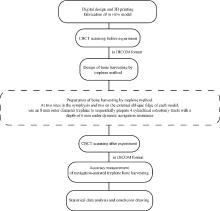

Accuracy of dynamic navigation-assisted trephine method for bone harvesting

Jiayu LIU, Ning ZHU, Yuchen CHANG, Xianming GAO, Yu ZHANG*( )

- Department of Oral Implantology, Peking University School and Hospital of Stomatology & National Center for Stomatology & National Clinical Research Center for Oral Diseases & National Engineering Research Center of Oral Biomaterials and Digital Medical Devices & Beijing Key Laboratory of Digital Stomatology, Beijing 100081, China